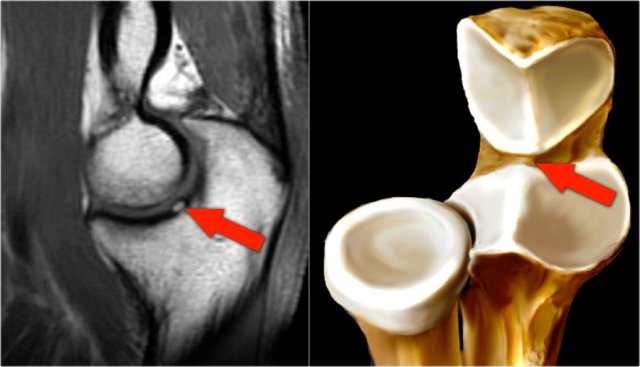

Pseudodefect of the capitellum

This is a finding that you frequently see on coronal images.

It looks like an osteochondral lesion, but if you look at the sagittal image you will notice that the coronal image runs through the posterior non-articular portion of the capitellum.

So when the elbow is fully extended, a portion of the radial head is actually behind the carticular surface of the capitellum.

On a coronal view we will be looking at the radial head which is covered with cartilage and opposite to it the non-cartilage covered part of the capitellum, which frequently is somewhat irregular.